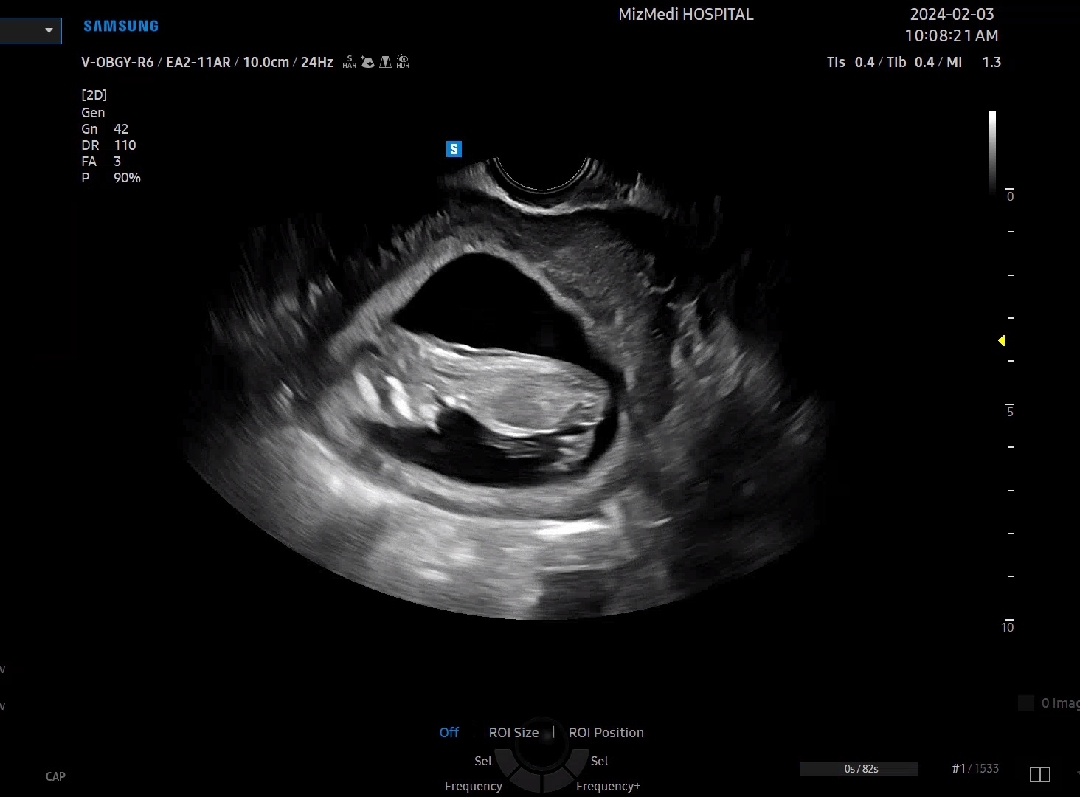

11주 5일 각도법 봐주세요~

촘파보다가 캡쳐했는데 제 눈에는 딸같은데 고수님들 함께 봐주세요~

개인적 의견이지만 딸이신것 같아요 ㅎㅎ